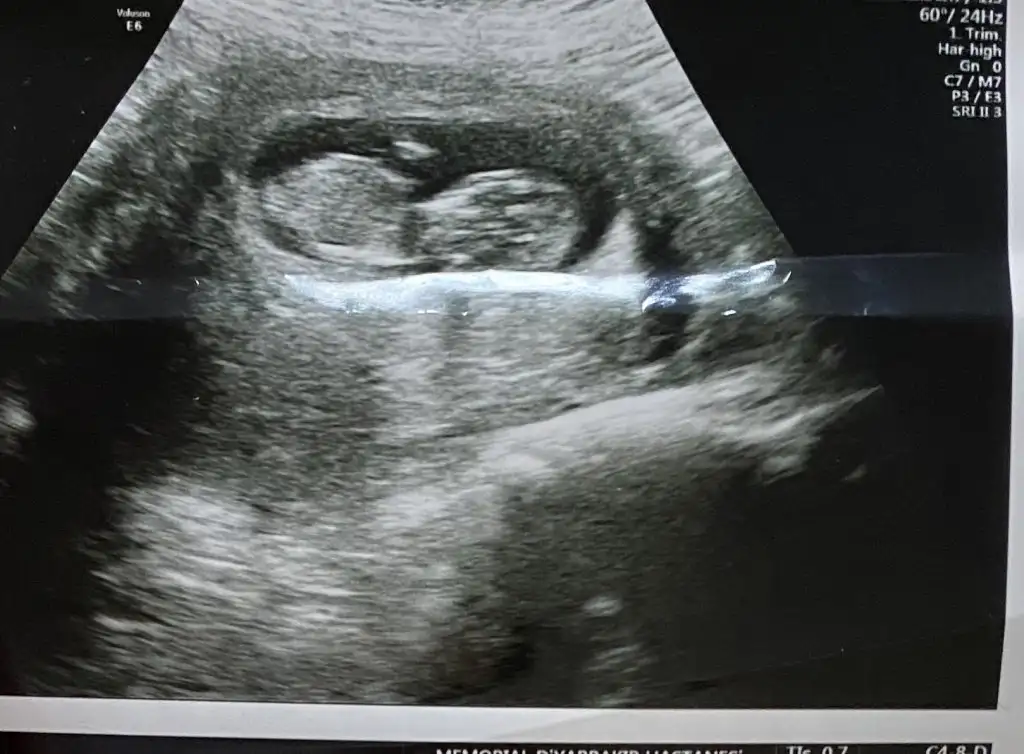

Dr emin olamadan bir tahmin yaptı ama buraya da atayım dedim 🥰 11+6 dedi 🥰

Valla doğrudur erken hafta genelde erkek tahminleri yalnış çıkıyormuş klitoris çıkıntısını pipi sanabiliyorlarmış ilerleyen haftalarda çıkıntı küçlp cinsel organın içinde kalıyor tabi pipiyse de sabit 😂